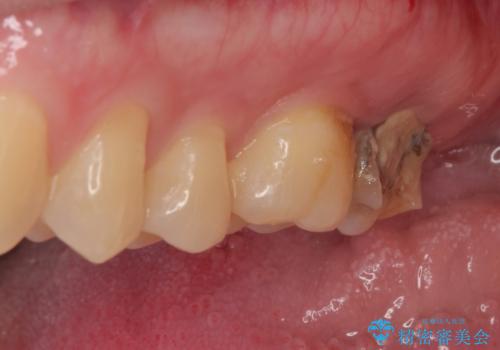

- 他院で虫歯治療の途中の歯を治療したいとのことで来院された患者様です。来院時特に症状もなく、根管治療途中の状態でした。レントゲン上でも大きい病変を認めました。治療方針として再度根管治療を行うか、抜歯をしてインプラントにする二つの方法をご提案しました。

咬み合わせが強く根管治療後の歯の破折のリスクや治療期間の観点からインプラント治療を行っていくこととなりました。

根尖病巣も大きかったため先に抜歯を行い、1ヶ月後にインプラントを埋入しました。